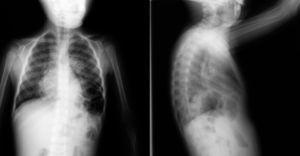

Con la sospecha clínica de neumonía, se realiza una radiografía de tórax donde se aprecia un aumento de densidad hiliar y perihiliar izquierda con desviación del mediastino hacia la derecha, objetivándose asas intestinales en hemitórax inferior izquierdo. Ante imagen sugestiva de defecto diafragmático (fig. 1), se solicita resonancia magnética (RM) que confirma la existencia de hernia diafragmática posterior izquierda (hernia de Bochdalek) con riñón izquierdo y asas intestinales en cavidad torácica (fig. 2).